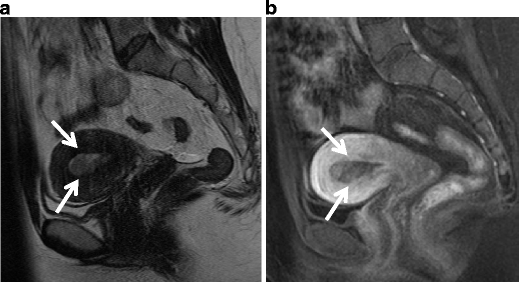

Serous carcinoma in a 55-year-old female. a Sagittal T2-weighted image demonstrates an endometrial tumor of decreased intensity occupying the endometrial cavity, and protruding into the external cervical os. Note the endometrial-myometrial border in both the corpus and cervix is diffusely obscured, suggesting myometrial invasion of the tumor (arrowheads). There is a small implant on the posterior serosal surface of the uterus (arrow). b Fusion image of DWI onto T2-weighted image exhibits increased intensity corresponding to the tumor in the endometrial cavity. The implantation on the posterior wall is also clearly demonstrated with excellent tissue contrast (arrowhead)

Endometrioid carcinoma in 69-year-old woman. a T2-weighted image demonstrates an ill-defined myometrial mass of decreased intensity (arrows). b Fusion image with DWI onto T2-weighted image shows increased intensity in the myometrial mass, which represents endometrioid carcinoma infiltrating into the myometrium